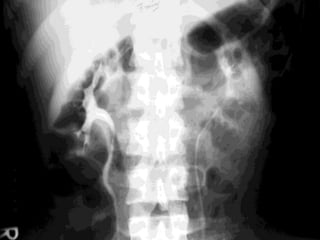

Imaging study

Chest x-ray

– Fracture lower posterior ribs

Abdomen and pelvis plain film

– Fracture transverse processes of lumbar

vertebrae

– Fracture pelvic bones